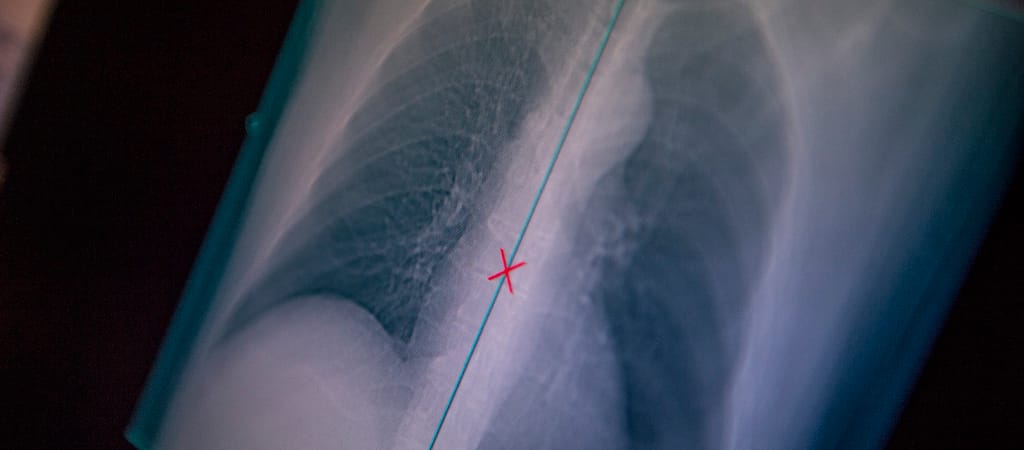

A TBC vagy gümőkór egy nagyon súlyos fertőző betegség, ami miatt évente 1,3 millió ember hal meg világszerte. Ennek azonban nem kellene így lennie, a betegség ugyanis – ha nem rezisztens kórokozó okozza – gyógyszerekkel gyógyítható. A brit Surrey Egyetem tudósai szerint azonban a betegek mintegy 50 százaléka nem tartja be az előírt, hosszan tartó (6-12 hónap) antibiotikum-kezelést.